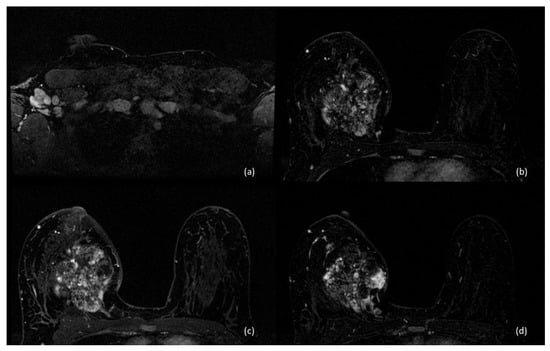

4. Imaging